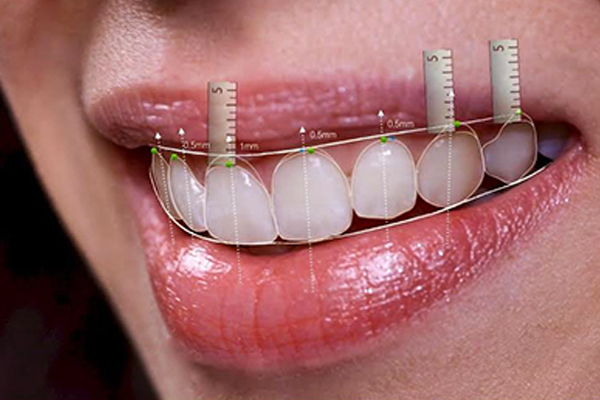

Geçmişte yılda 1-2 defa diş temizletmek hariç dişin görünüşünü düzeltmek için yapılabilecek çok şey yoktu. Ama son 25 yılda diş hekimliğindeki malzeme, teknoloji ve restoratif tekniklerdeki gelişmeler, bizim, orijinali kadar güçlü ve renk değişimlerine dirençli dişlere sahip olabilmemizi sağladı. Eğer gülüşünüzü aydınlatmak veya bozuklukları düzeltmek istiyorsanız muhtemelen bugüne kadarki en iyi dönemde yaşıyoruz ve estetik diş hekimliği prosedürleri şu an çok revaçta…